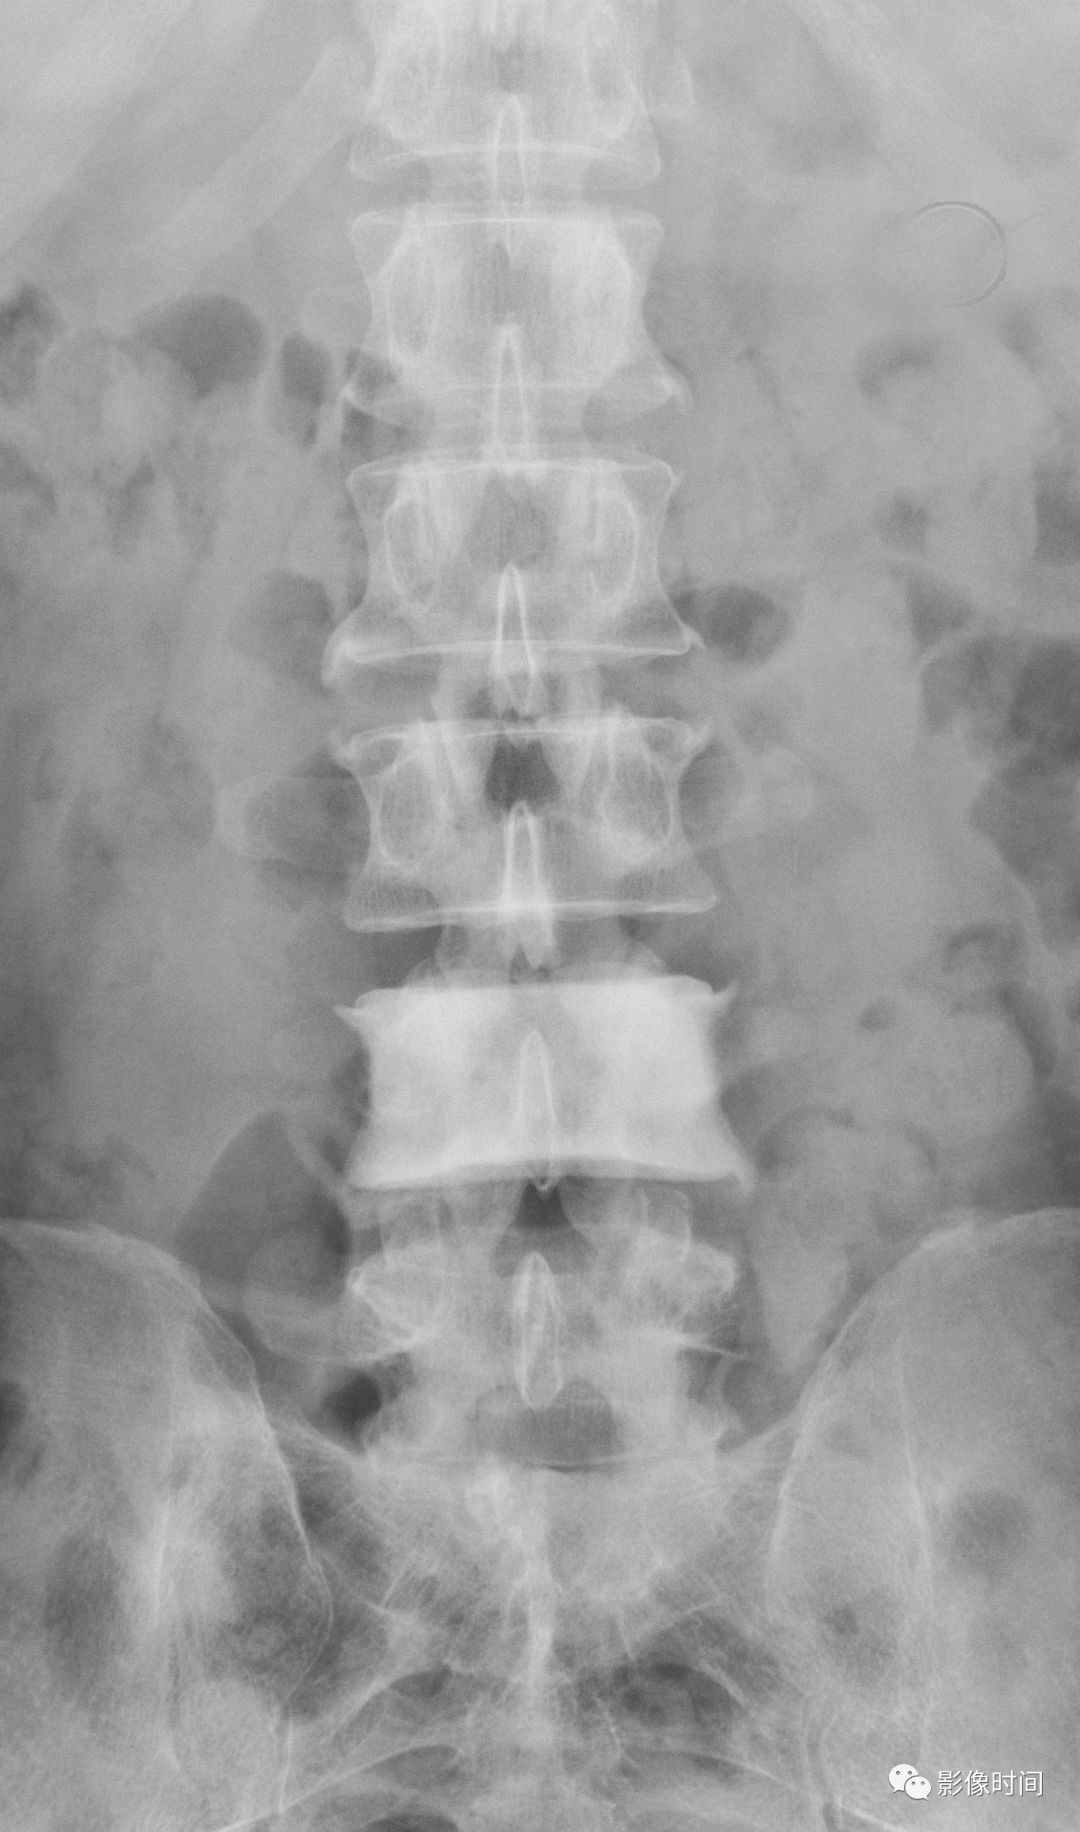

19竹节椎

竹节椎(Bamboo spine)

竹节椎是用于描述强直性脊柱炎的一个放射学特征,由于椎旁韧带广泛骨化,导致椎体融合强直,这种薄而连续的韧带骨化在正位片使得脊柱的轮廓呈现波浪起伏状,宛如具有多个竹节的一根竹竿,故而得名。

典型病例

强直性脊柱炎。腰椎正位片示腰椎韧带、小关节囊广泛骨化,骨性强直,呈典型竹节椎表现。另可见骶髂关节骨性融合。

引用自:https://radiopaedia.org/ articles/ bamboo-spine-ankylosing-spondylitis